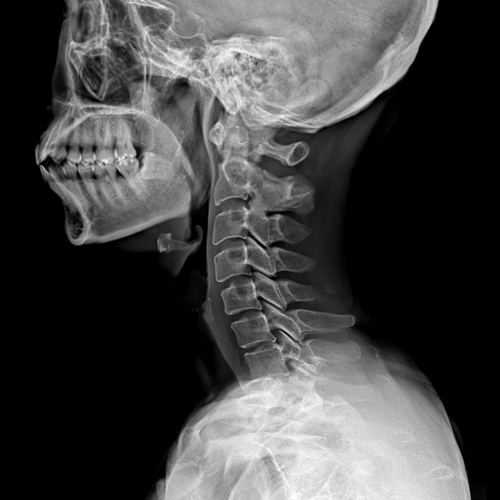

목디스크는 의사의 진찰 소견이 중요합니다.

단순 방사선 촬영은 목 디스크를 보다 강력하게 의심하는 방법은 되지만 확진은 어렵습니다.

근전도 검사가 의료 보험 적용이 되는 디스크 확진 방법이며, MRI는 영상으로 목 디스크가 뒤로 밀린 것을 확인할 수 있습니다.